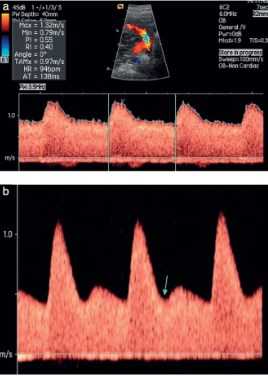

Рис.2. Допплерография маточной артерии, проведена трансабдоминально во втором триместре беременности. Нормальные (а) и патологические (b) формы кривой; дикротическая выемка (стрелка) (b).

Оценка маточной артерии во втором триместре беременности (Рис.2)

Рис.3. Допустимые (а) и недопустимые (b) формы кривой при проведении допплерографии в пупочной артерии. На сонограмме b графические изображения кривой слишком малы, а скорость слишком медленная.

Рис.4. Допплерография артерии пуповины получена у того же плода с интервалом 4 мин. Наблюдаем: (а) нормальный кровоток и (b) очень низкий диастолический кровоток, что связано с неправильным использованием фильтра стенки сосуда.

- Фильтр стенки сосудов (или “фильтр верхних частот”) используется для устранения шума от движения стенок сосудов. Он должен быть установлен как можно ниже (≤ 50-60 Гц) с тем, чтобы устранить низкочастотный шум из периферических кровеносных сосудов. При использовании более высокого фильтра могут быть созданы ложные эффекты (рис. 4б).